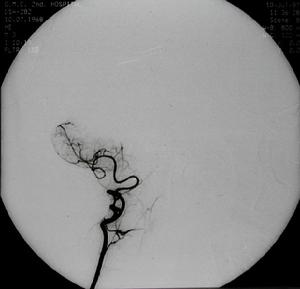

2.數字減影血管造影(DSA)重點觀察主動脈弓兩側鎖骨下動脈及頸總動脈等血管。若發現鎖骨下或頭臂幹上,椎動脈起始部的近心段有嚴重狹窄(多為管腔的85%)或幾乎閉塞,甚至同時可見造影劑經對側椎動脈上行至基底動脈又下行(逆流)至患側鎖骨下動脈的遠心段更可確診。

主動脈縮窄SSS確診主要靠腦血管造影,為避免血管造影時引起椎動脈起始段功能性狹窄,有條件的地方,最好行全腦血管造影以明確診斷。經股動脈穿刺腦血管及患側上肢血管造影可明確閉塞部位,有利於外科手術治療。對於急性鎖骨下動脈閉塞者,最好於閉塞後3天內行取栓術,有利於血液再通,避免再次栓塞。本組1例取栓術後至今已4年,配合抗凝治療,未再出現缺血症狀。大多數作者對SSS手術治療有較好的評價,鎖骨下與頸總動脈架橋術,是治療本症最常用的方法。對於少數長期狹窄的SSS患者且無急性腦損害者,尤其是壯年患者,可試用抗血小板聚集劑(6個月或以上)以及病因治療觀察。經顱多普超聲(TCD)可以連續及動態觀察椎動脈、基底動脈血流方向和速度,觀察顱內其他動脈被盜血的影響程度,是盜血綜合徵的敏感指標,可以評價治療效果和隨診。